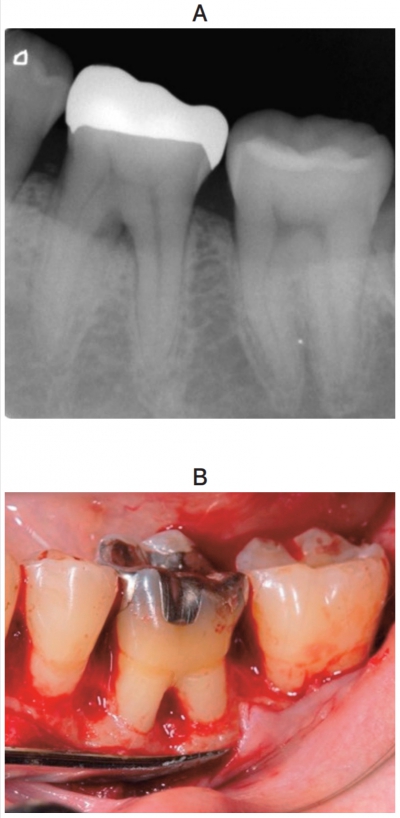

55歳の男性。左側の下顎大臼歯部の咬合時の違和感を主訴として来院した。歯周基本治療後の再評価検査で、⎾6 の分岐部では頰側から水平方向にポケット探針が4mm 入るが貫通はしない。GTR法による歯周組織再生療法を行うこととした。初診時のエックス線写真と歯周外科治療時の口腔内写真を別に示す。再評価時の歯周組織検査結果の一部を表に示す。

GTR膜設置前に行うのはどれか。2つ選べ。